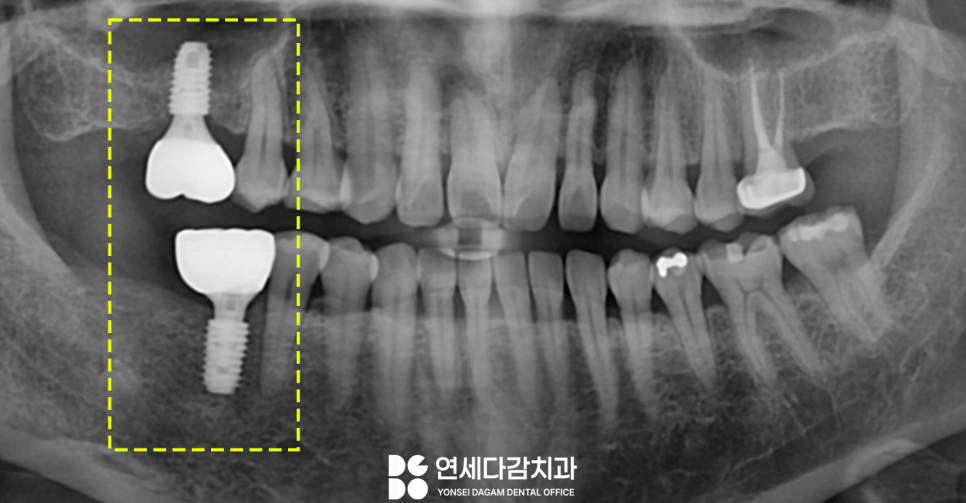

오른쪽 위아래 어금니 부위에

이가 결손된 채로 방치하고 있다가

임플란트를 진행하게 된 케이스입니다.

오랜 기간 방치된 탓에

자극을 받지 못한 잇몸뼈가 흡수되어

움푹 들어간 모습을 확인할 수 있습니다.

기존 수직골이 3미리도 안되던 뼈가

거상 후 3배 정도 많아진 것을

엑스레이를 통해 알 수 있었습니다.

맞은편 결손된 공간은

단순 식립을 통해

위아래 어금니 부위 모두

치료를 완료하였습니다.